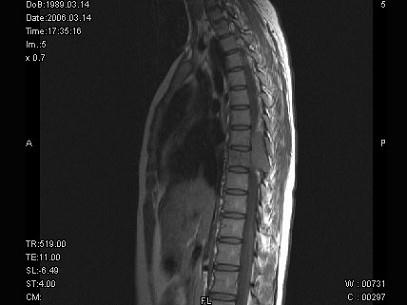

问题 女,18岁,腰以下麻木、双下肢无力,行走困难。PE:双下肢肌力IV+级,肌张力高,腱反射活跃,T以下痛觉消失,深感觉减退,请根据所提供图像,选择最可能的诊断 ( )

选项 A、脊膜瘤 B、淋巴瘤 C、骨母细胞瘤 D、骨巨细胞瘤 E、神经鞘瘤

答案 D